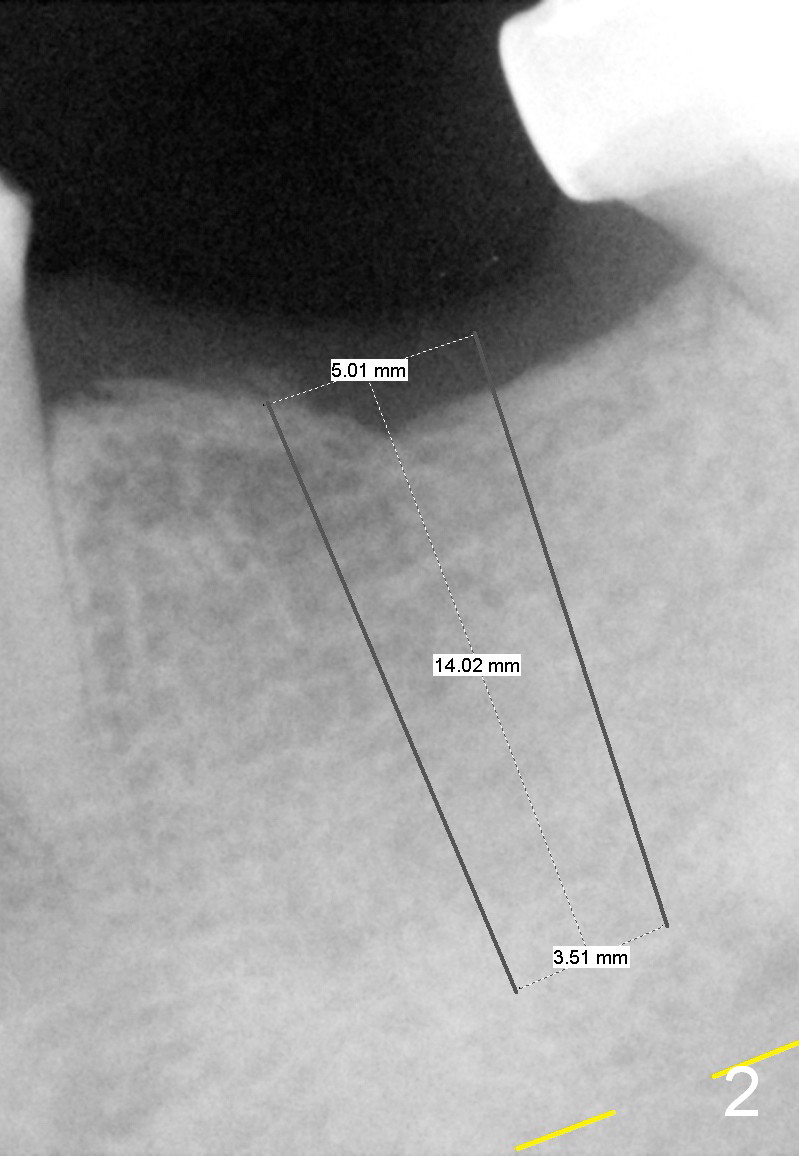

A 45-year-old man has lost the tooth #19 for about a decade (Fig.1). In spite of this, the ridge is not particularly narrow. The bone height is good for 14 mm bone-level implant (Fig.2). After incision, initial osteotomy depth is 12 mm. Insert a short parallel pin for occlusal check and a depth-marked parallel pin for X-ray. When the depth is adjusted, use drills with stoppers to finish osteotomy. If bone density is low, the drill is one size smaller than the expected implant.